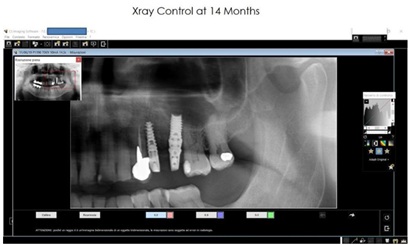

Rx details in figure 28.

Figure 28: Left Side and Right Side note: the red arrows were the old sinus pavment and the yellow arrows, the new sinus pavment.